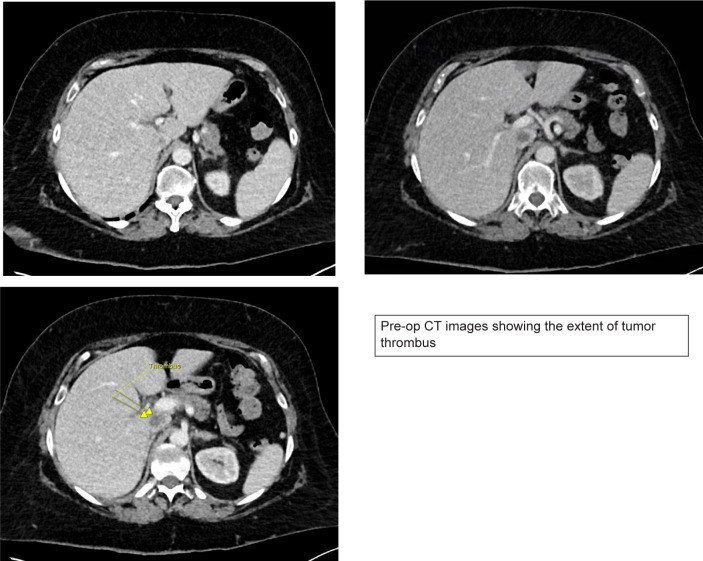

Intraoperative tumor thrombus embolization is a potentially lethal complication during inferior vena cava (IVC) thrombectomy for renal cell carcinoma (RCC). Intraoperative embolization is uncommonly encountered because IVC thrombectomy surgical technique is focused on avoiding this complication. Nonetheless, early recognition of embolization is essential so that emergent management can be instituted. When available, cardiopulmonary bypass (CPB) and embolectomy should be considered the gold standard for the management of intraoperative embolization. Several novel endovascular techniques are also available for selective use. We present the case of a 71-year-old female with a right renal mass and level II (retrohepatic) IVC tumor thrombus. During cytoreductive nephrectomy and IVC thrombectomy, tumor embolization was diagnosed during a period of hypotension based on transesophageal echocardiographic finding of new thrombus within the right atrium. This prompted sternotomy, CPB, and pulmonary artery embolectomy. The patient survived this embolization event and has a complete response to systemic therapy 9 months postoperatively. This case serves as the framework for a discussion on management considerations surrounding intraoperative embolization during IVC thrombectomy.

Abstract Image